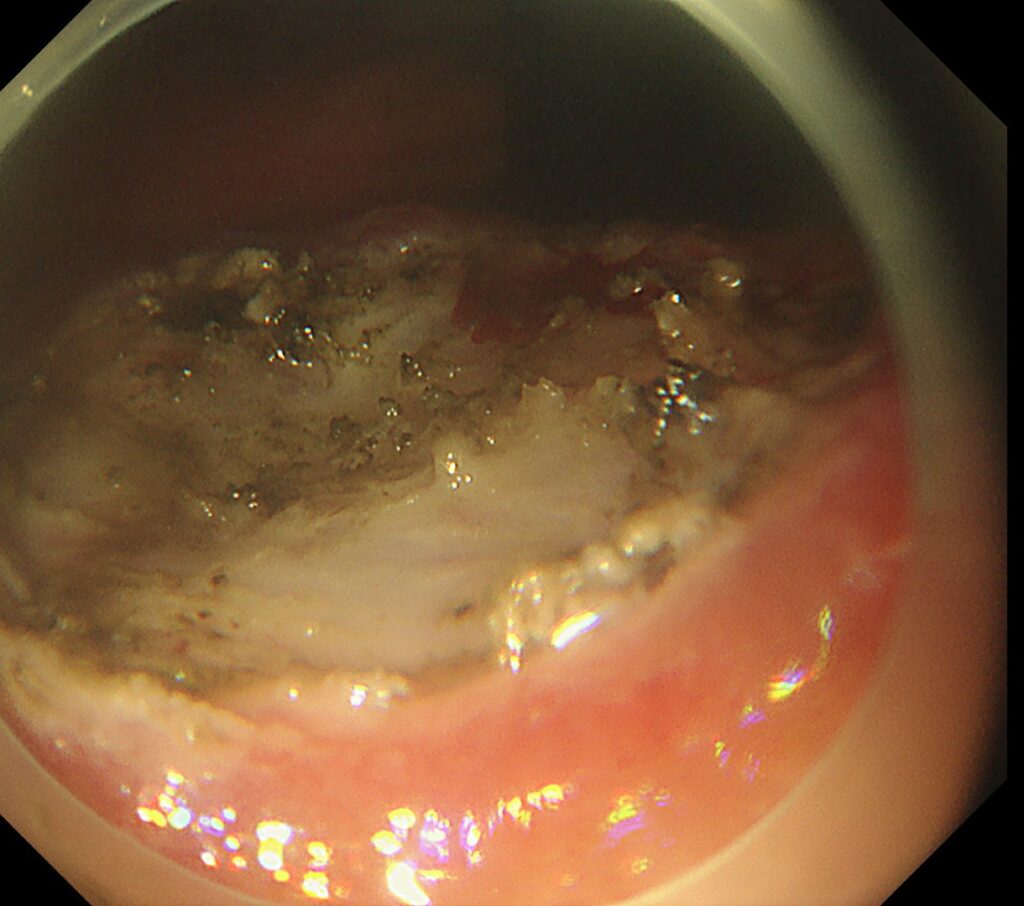

予想通り、筋層と病変が強固に癒着し、通電するスペースがごくわずかしかない状況。なお、使用した局注はもちろん、ヒアルロン酸です。

剥離に関しては、筋層を損傷しないように、繊維を1本ずつ剥がしていくように進めていきます。

筋層と線維化領域を見極めないと、穴が空き緊急手術となる場面ですが、豊富な経験と臨床的嗅覚を活かし、病変切除成功となっております。

潰瘍底をみれば、エキスパートの先生であれば、察すると思いますが、強烈な線維化(癒着)症例でした。